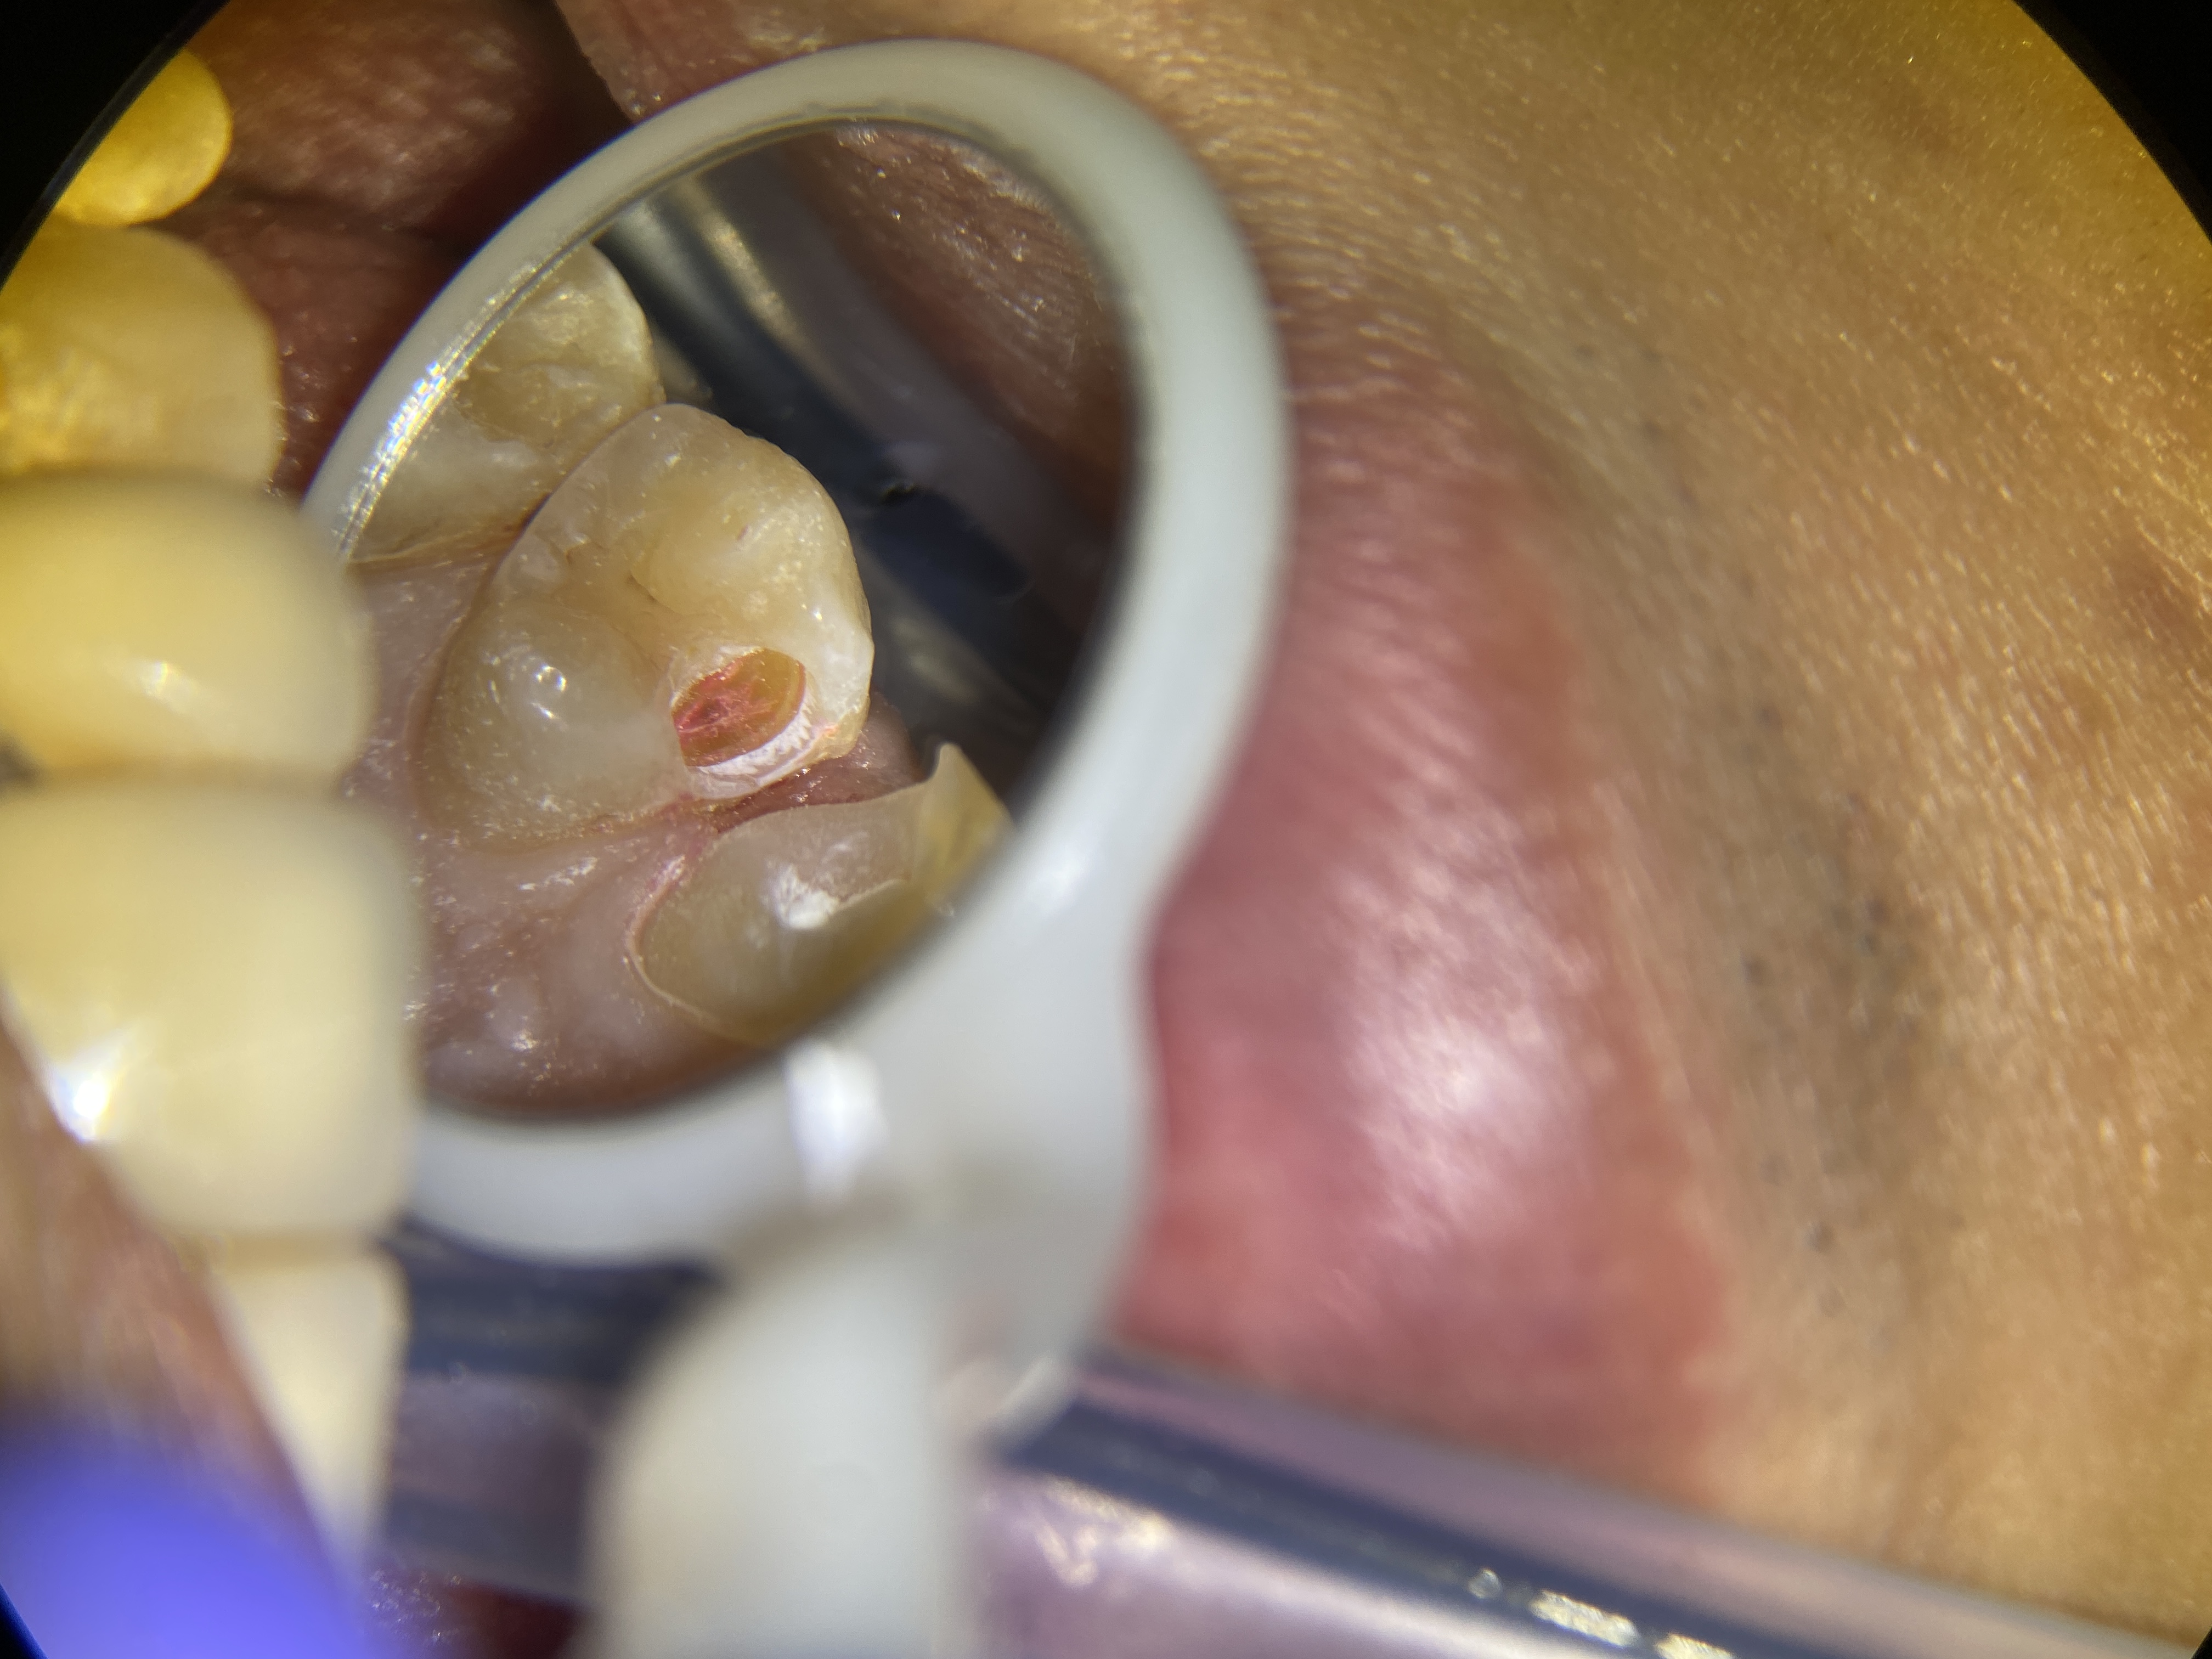

古い詰め物が歯と歯の間にあり、フロスを通すと引っかかって気になるとのことで、詰め物を削ったら中が虫歯になっていました💦(ピンク色に染まっている所が虫歯です😈)

虫歯を取っていくと神経が露出するギリギリのところでした。